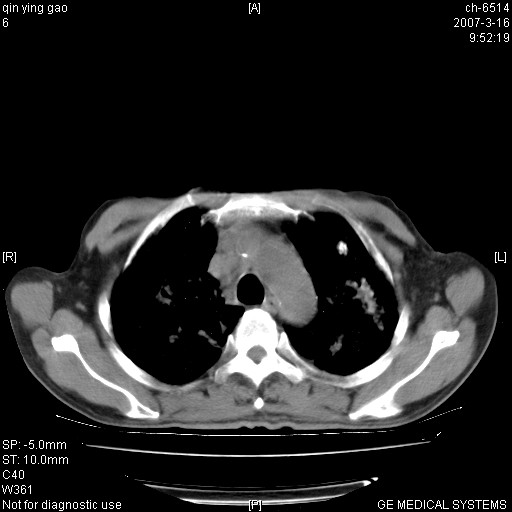

男,64岁.乏力2个月,畏寒、发热1月余。体重下降。血沉加快,白细胞不高。

双肺以中上肺野为著斑片状.结节壮密度增高影 左上肺前段可见小类圆钙化灶 纵隔淋巴结无明显肿大

双肺可见大小不等结节状密度增高影,密度不均,分布不均(双肺上叶为著),亚急性血行播散性肺结核.

(本例特征:以大小不等结节为主,主要分布在双上肺,并部分病灶融合成较大结节,期间搀杂诸多细小结节。从病灶特点与分布形式分析,更趋向于感染。)

两中上肺见有广泛分布大小不一的结节灶及斑片状影,部分融合,双下肺未见异常密度影,纵隔无明显肿大淋巴结,血沉加快,白细胞不高,首先考虑结核。 建议结合ppd检查或痰培养排除其他非特异性炎症。

中上肺野密布棉团状影,以胸膜下区为界,边缘模糊,可能是小叶或腺泡渗出及实变。全肺野弥漫分布网线样影及细小粟粒样影,可能是细支气管炎及间质内炎症。综合分析应首先考虑气道播散性感染,而肺内多处斑点性钙化,强烈提示陈旧结核复发并支气管播散。建议详细讯问病史